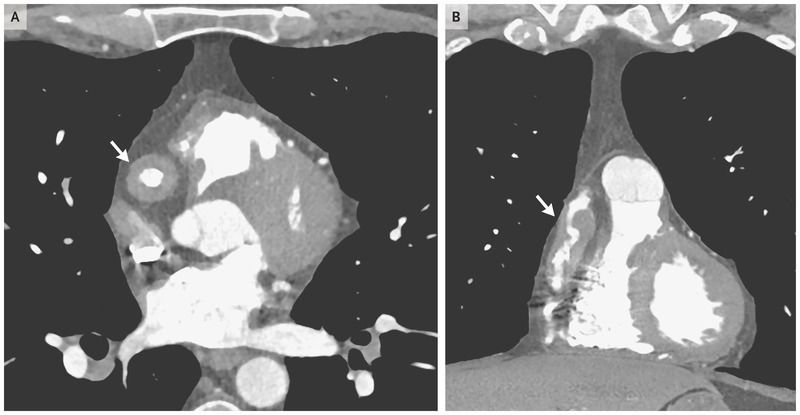

A 47-year-old man presented to the cardiology clinic for evaluation of coronary-artery dilatations that had been detected on computed tomography (CT) of the chest performed as a follow-up examination of pulmonary nodules. The patient was asymptomatic but had a history of biopsy-proven IgG4-related disease involving the pancreas and the lacrimal and parotid glands. At the current presentation, he had no swelling of the lacrimal or parotid gland or abdominal tenderness, all of which had characterized previous disease flares. He had been receiving rituximab for the past 4 years. Results of laboratory tests showed a normal erythrocyte sedimentation rate and serum IgG4 concentration. An electrocardiogram-gated CT angiogram of the coronary vessels revealed aneurysmal dilatation of the right coronary artery with marked, nearly circumferential, periarterial soft-tissue thickening in the transverse view (Panel A, arrow) and the coronal view (Panel B, arrow). Diffuse thickening and aneurysmal changes were also seen in the left anterior descending coronary artery. The thoracic aorta, branch vessels of the aortic arch, and abdominal aorta showed no evidence of disease. It was assumed that these abnormalities occurred during the earlier period of active disease and represented damage rather than active IgG4-related disease. Treatment with low-dose aspirin was started. At a follow-up examination 4 months later, the patient remained asymptomatic.